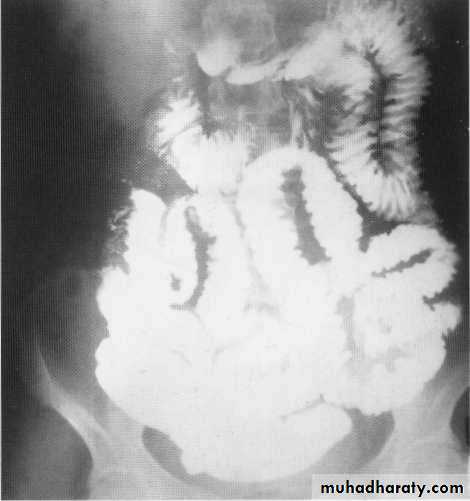

Small bowel contrast study

Barium follow throw x- rayCt scan with oral contrast

Small bowel lymphoma